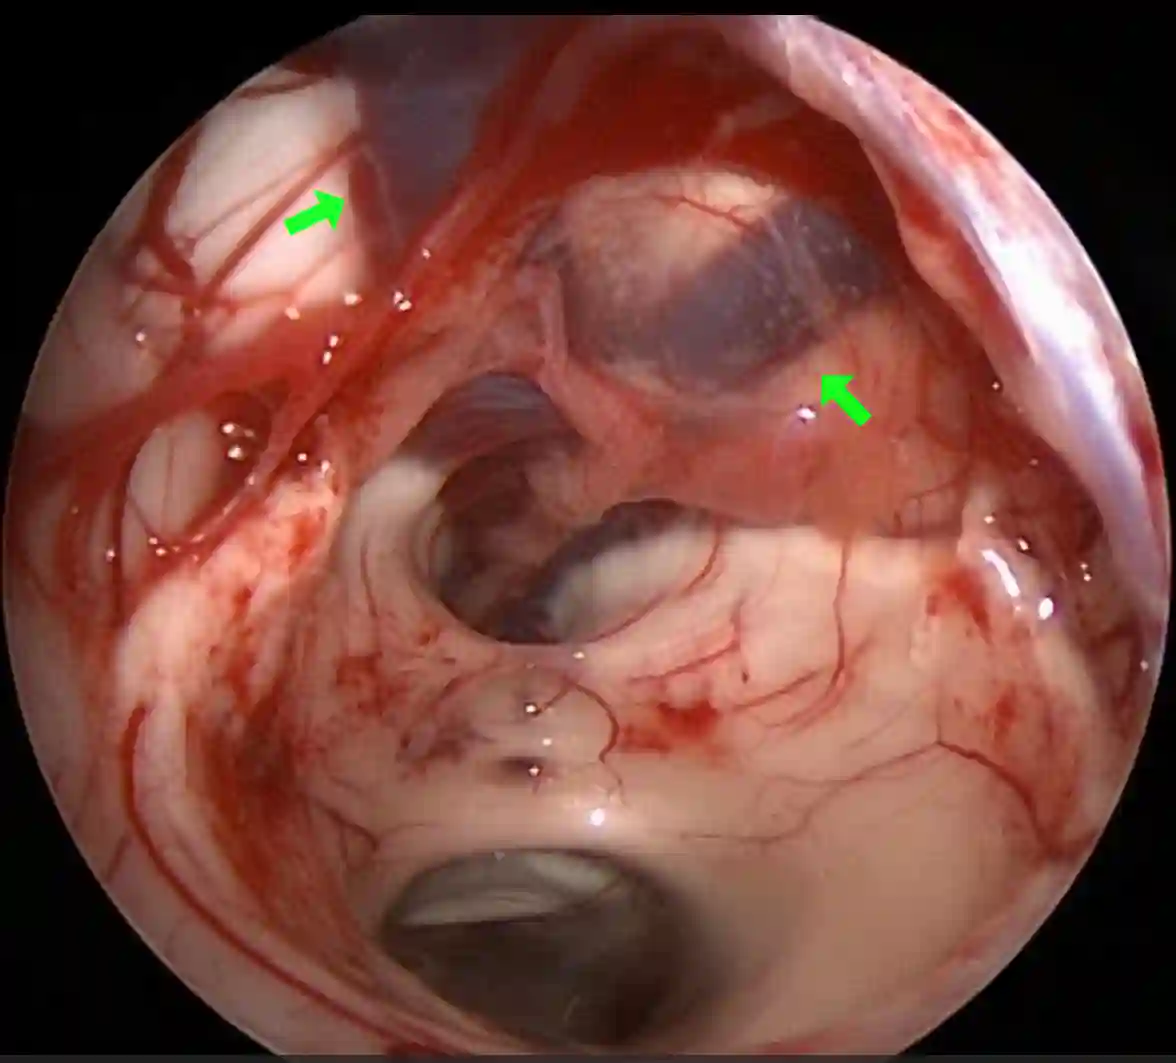

Abbildung

Bildgebung